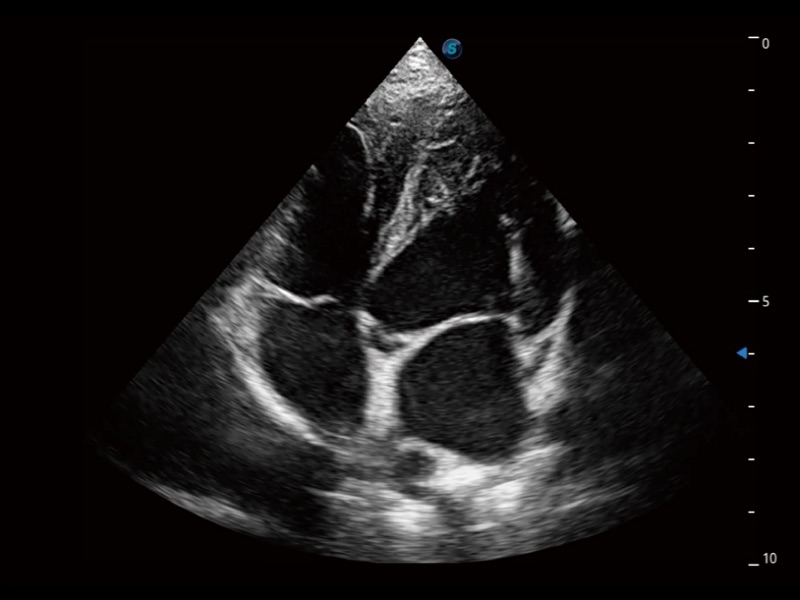

ProPet 70专为动物医生设计,对不同的动物体型和生理结构作出了针对性的优化。通过动物影像专用软件,可满足个性化的应用需求,帮助动物医生获得更精确的诊断数据。

当心脏测量结果超出正常范围时,可实时预警提示动物医生,减少疾病漏诊概率。